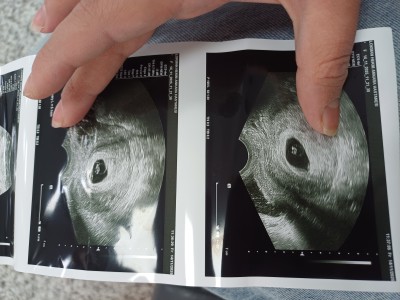

Kızlar ben son regl tarihmden hesapla 7+4de gittim doktora bebek oluşmuş kese çapı 15mm kalp atışı yoktu 10 gün sonra gel dedi geç döllenme ola bilir bebek daha 5 haftalık dedi dün gittim 8+5 olyor son adet tarihimden hesaplandığında yine de kalp atışını duyamadık 4 gün sonra gel dedi son kes dinleyelim kese boyum hocamın dediğine göre 18mm olmuş bebek de 5mm olmuş 7 mm kadar duyulur duyulmazsa alıcaz dedi ama ultrosan fotoda aşağıda kese ölcüm 33mm çıkıyor böyle bişey başına gelmiş var mı